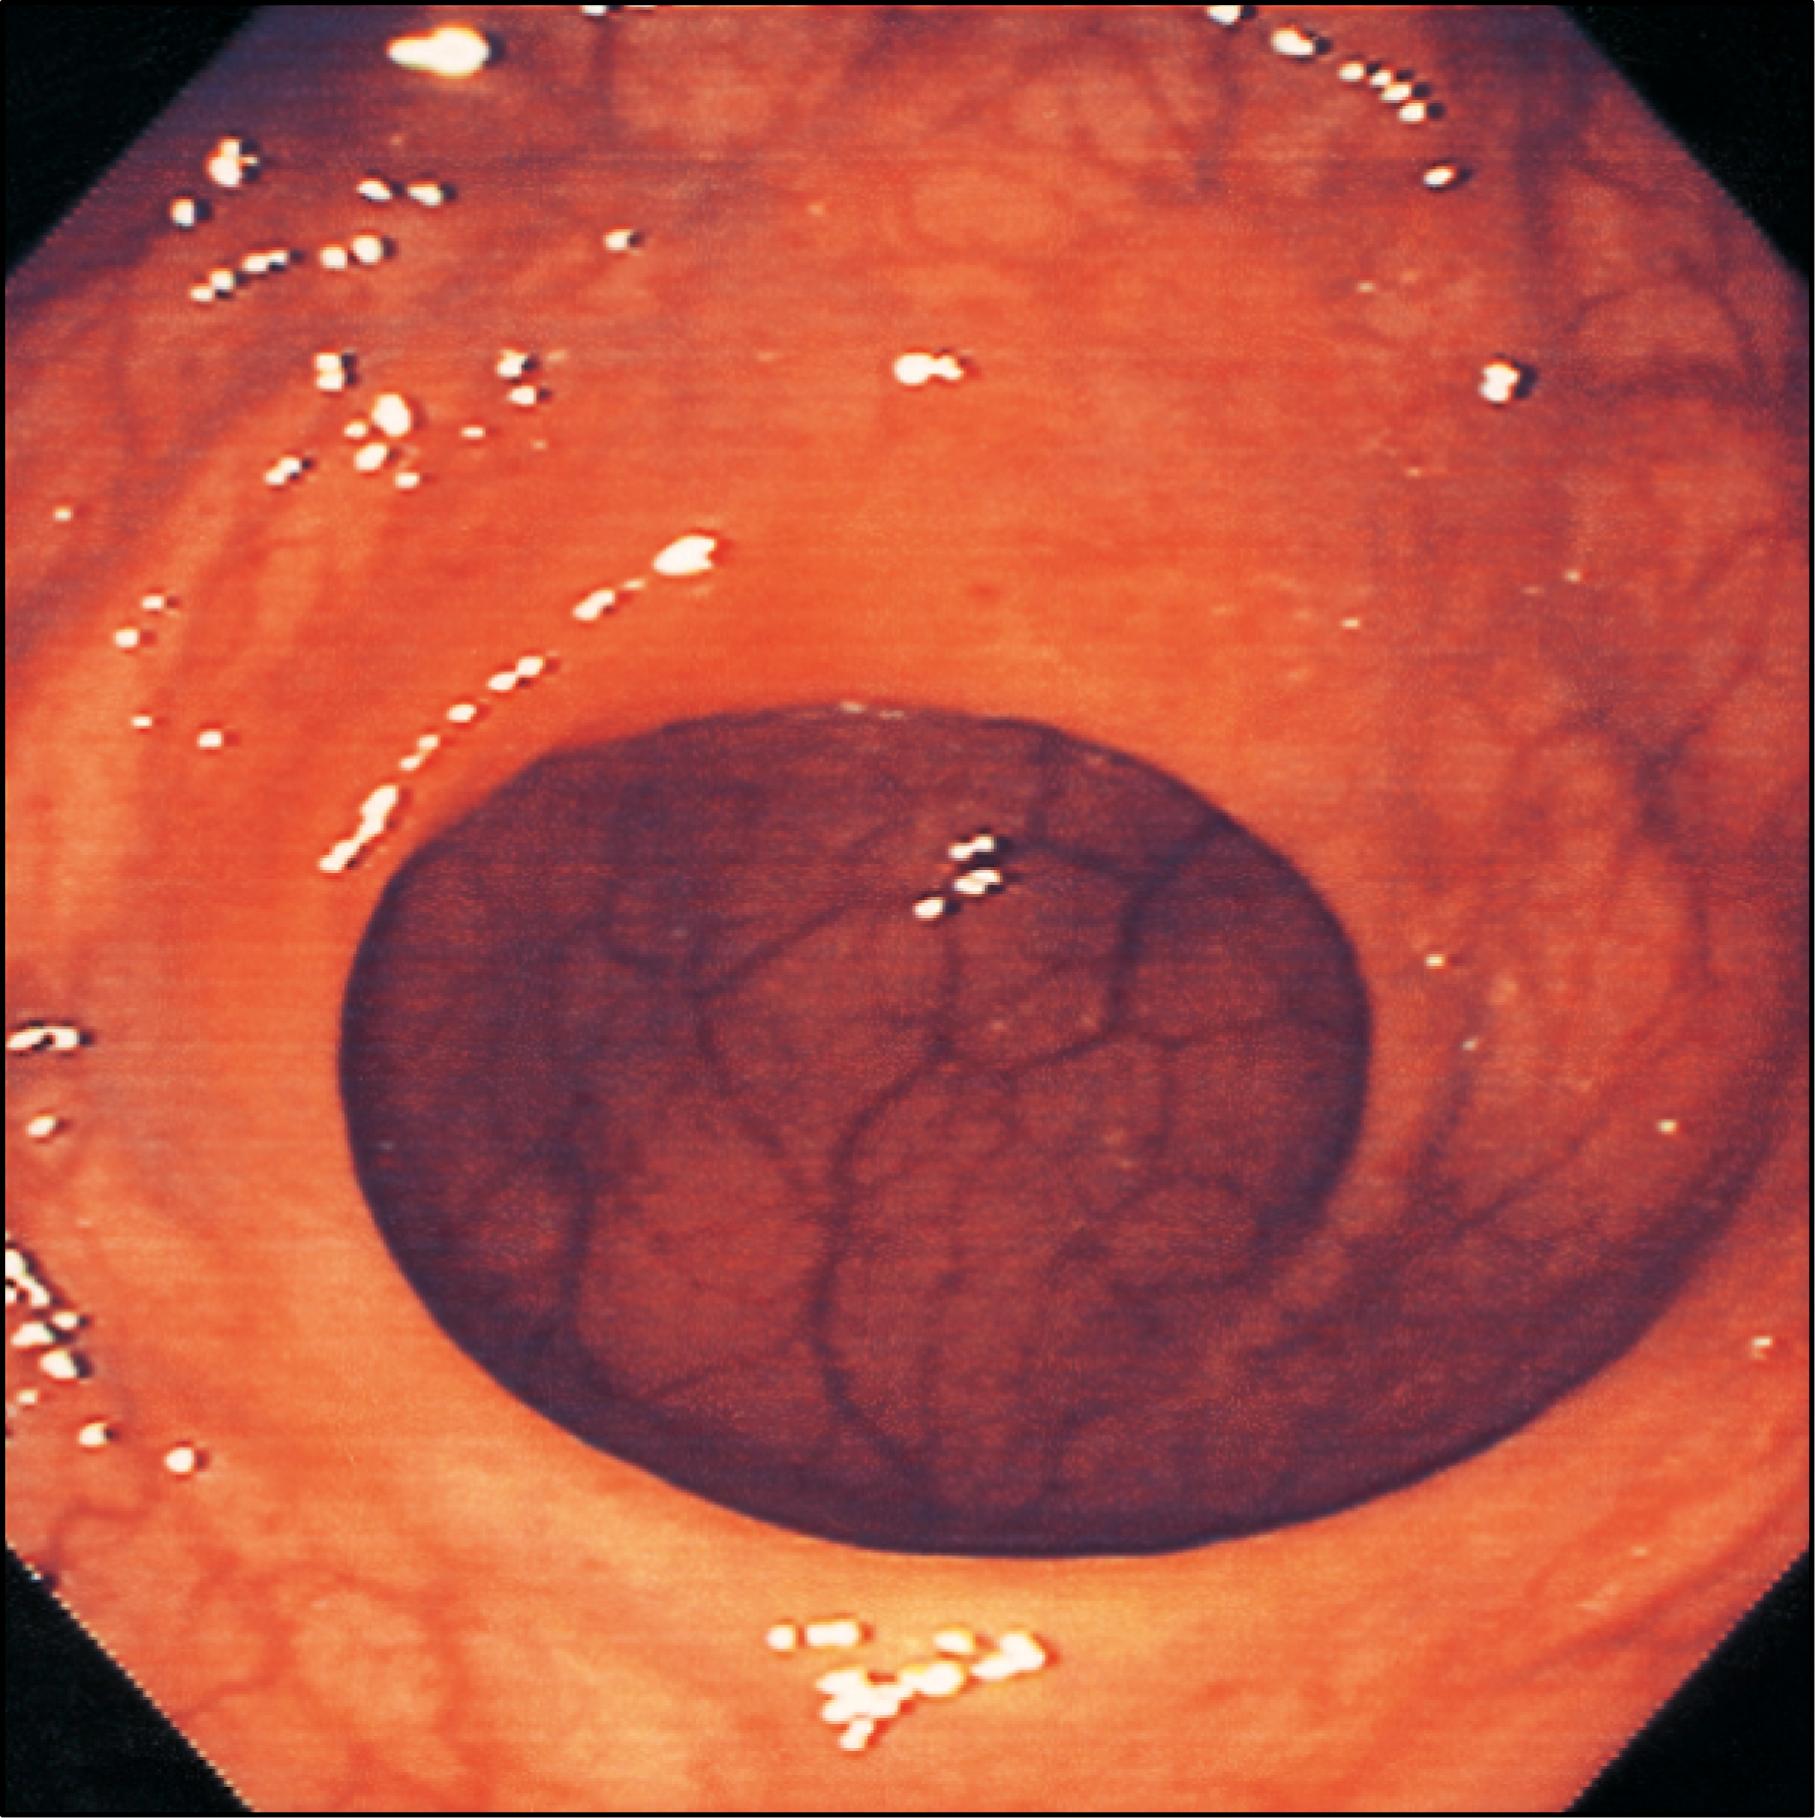

The haustra of the colon represent sites where the mucosa and submucosa of the colonic wall are infolded; these folds partially span the lumen of the colon but never form a complete circumferential ring. The pattern of haustra and appearance of the colonic mucosa help the clinician appreciate the level reached during flexible endoscopic examinations of the colon ( ). In the caecum, the three taeniae coli converge to form a characteristic ‘trefoil’ pattern on the caecal wall ( Fig. 65.4 ). The distal caecum is usually devoid of haustra, although a spiral mucosal pattern is often seen in the region of the orifice of the appendix ( Fig. 65.5 ). The ileal orifice can be identified as a thickened fold ( Fig. 65.6 ) and can be cannulated endoscopically to examine the terminal ileum. In the distal caecum and ascending colon, the haustra can extend across one-third of the lumen. In the transverse colon, the haustra often confer a triangular appearance to the cross-section of the lumen when it is viewed along its axis at colonoscopy ( Fig. 65.7 ). The haustra of the descending and sigmoid colon tend to be thicker and shorter, producing a more circular lumen cross-section ( Figs 65.8 65.9 ) . The wall of the colon is thinnest in the region of the caecum and ascending colon, where it is at risk of perforation during therapeutic endoscopic procedures. The overall luminal diameter is often smallest in the descending colon. The tortuosity of the sigmoid colon means that shorter lengths of it are visible during endoscopy than elsewhere in the colon. The haustra of the rectum usually form consistent and recognizable transverse rectal folds (spiral valves of Houston) and the submucosal vessels tend to be more pronounced than in the colon ( Fig. 65.10 ) . Most patients are found to have two or three folds and these are useful landmarks for planning rectal surgery ( ). Distinct veins are usually visible during endoscopy, and are most marked above the anorectal junction. FLOAT NOT FOUND FLOAT NOT FOUND FLOAT NOT FOUND FLOAT NOT FOUND

Fig. 65.9, The endoscopic appearance of the sigmoid colon; note the characteristic multiple large mucosal folds.